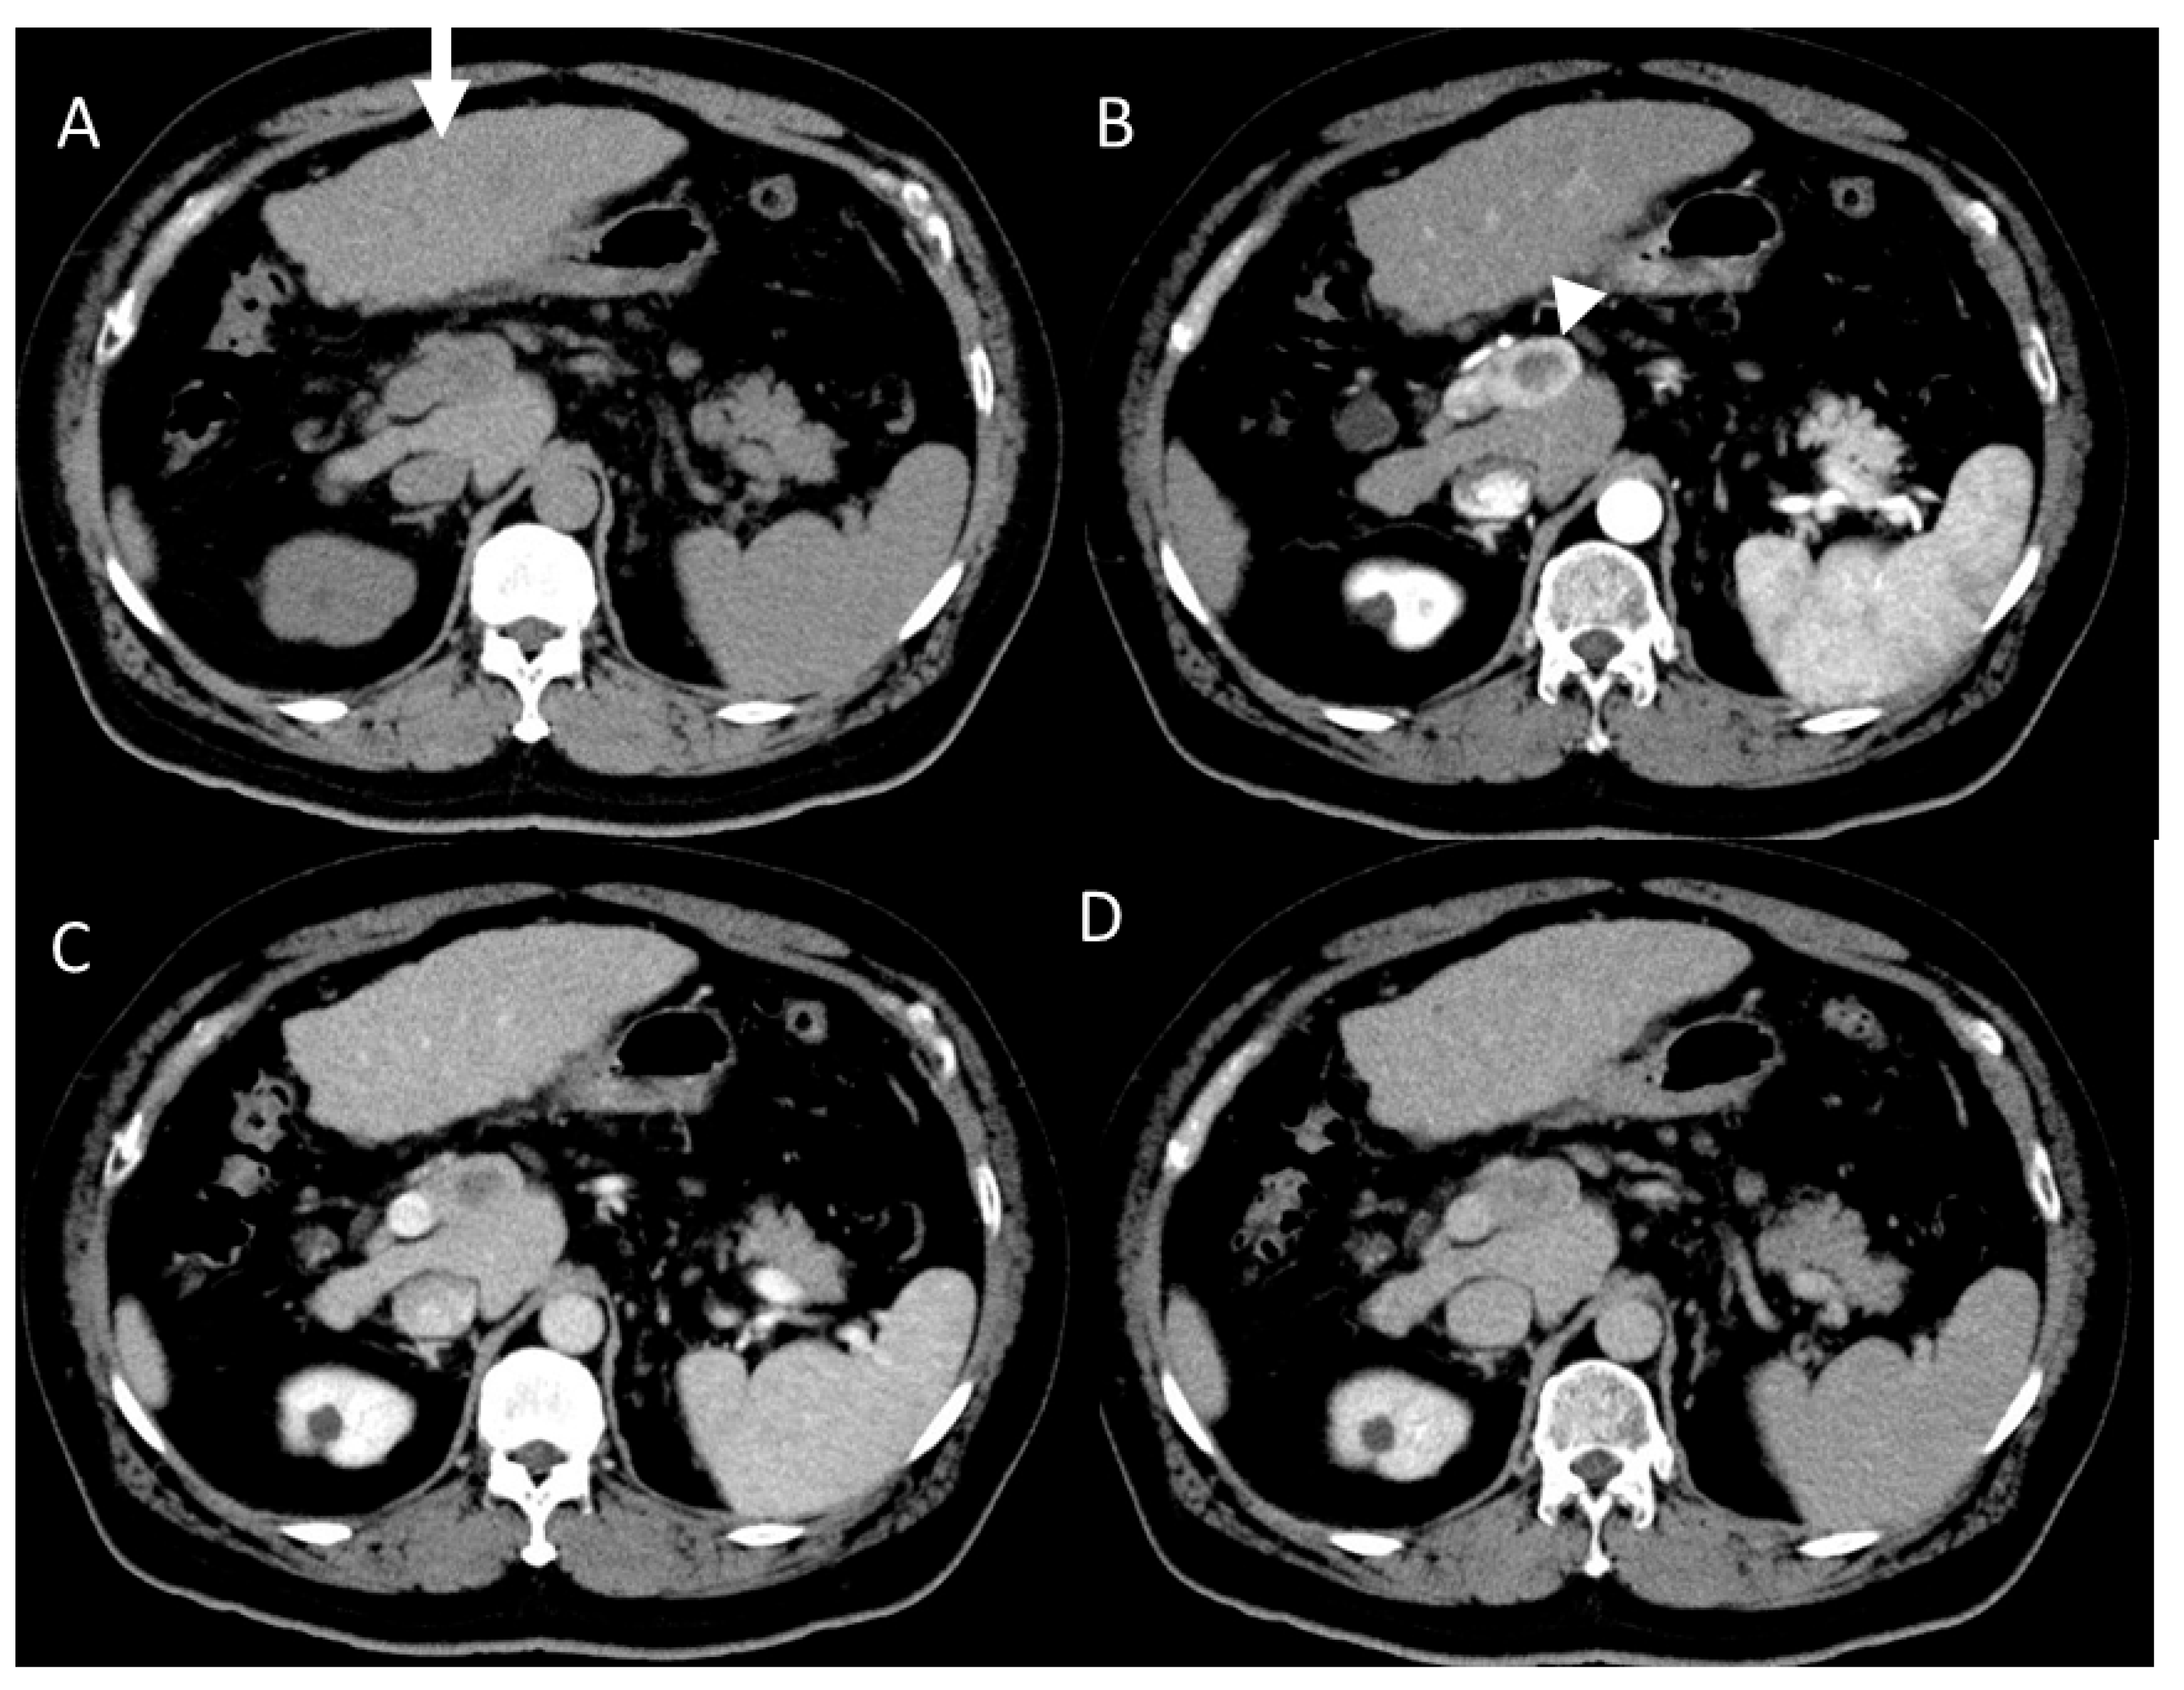

2.1. HCC Imaging on CT

4.7. Combined Hepatocellular and Cholangiocarcinoma (cHCC-CCA)

4.8. Steatohepatitic HCC (SH-HCC)